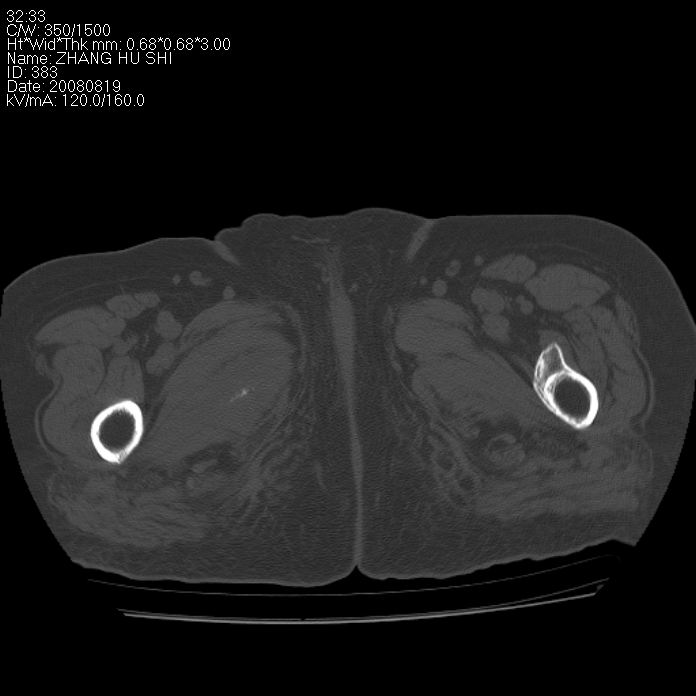

标题: CT15287:女 93岁 右髋关节疼痛 原左侧粗隆间骨折 CT发现右耻 [打印本页]

标题: CT15287:女 93岁 右髋关节疼痛 原左侧粗隆间骨折 CT发现右耻

支持转移

支持转移并周围软组织侵犯右闭孔内肌侵犯,但tb不能完全除外。